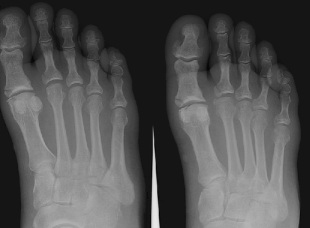

Have you paid attention to how you walk? When you walk normally, the foot comes down on the heel. It then rolls toward the toes. A lot of things are going on inside your foot through all of this. Take a look at the drawing and x-rays of a foot.